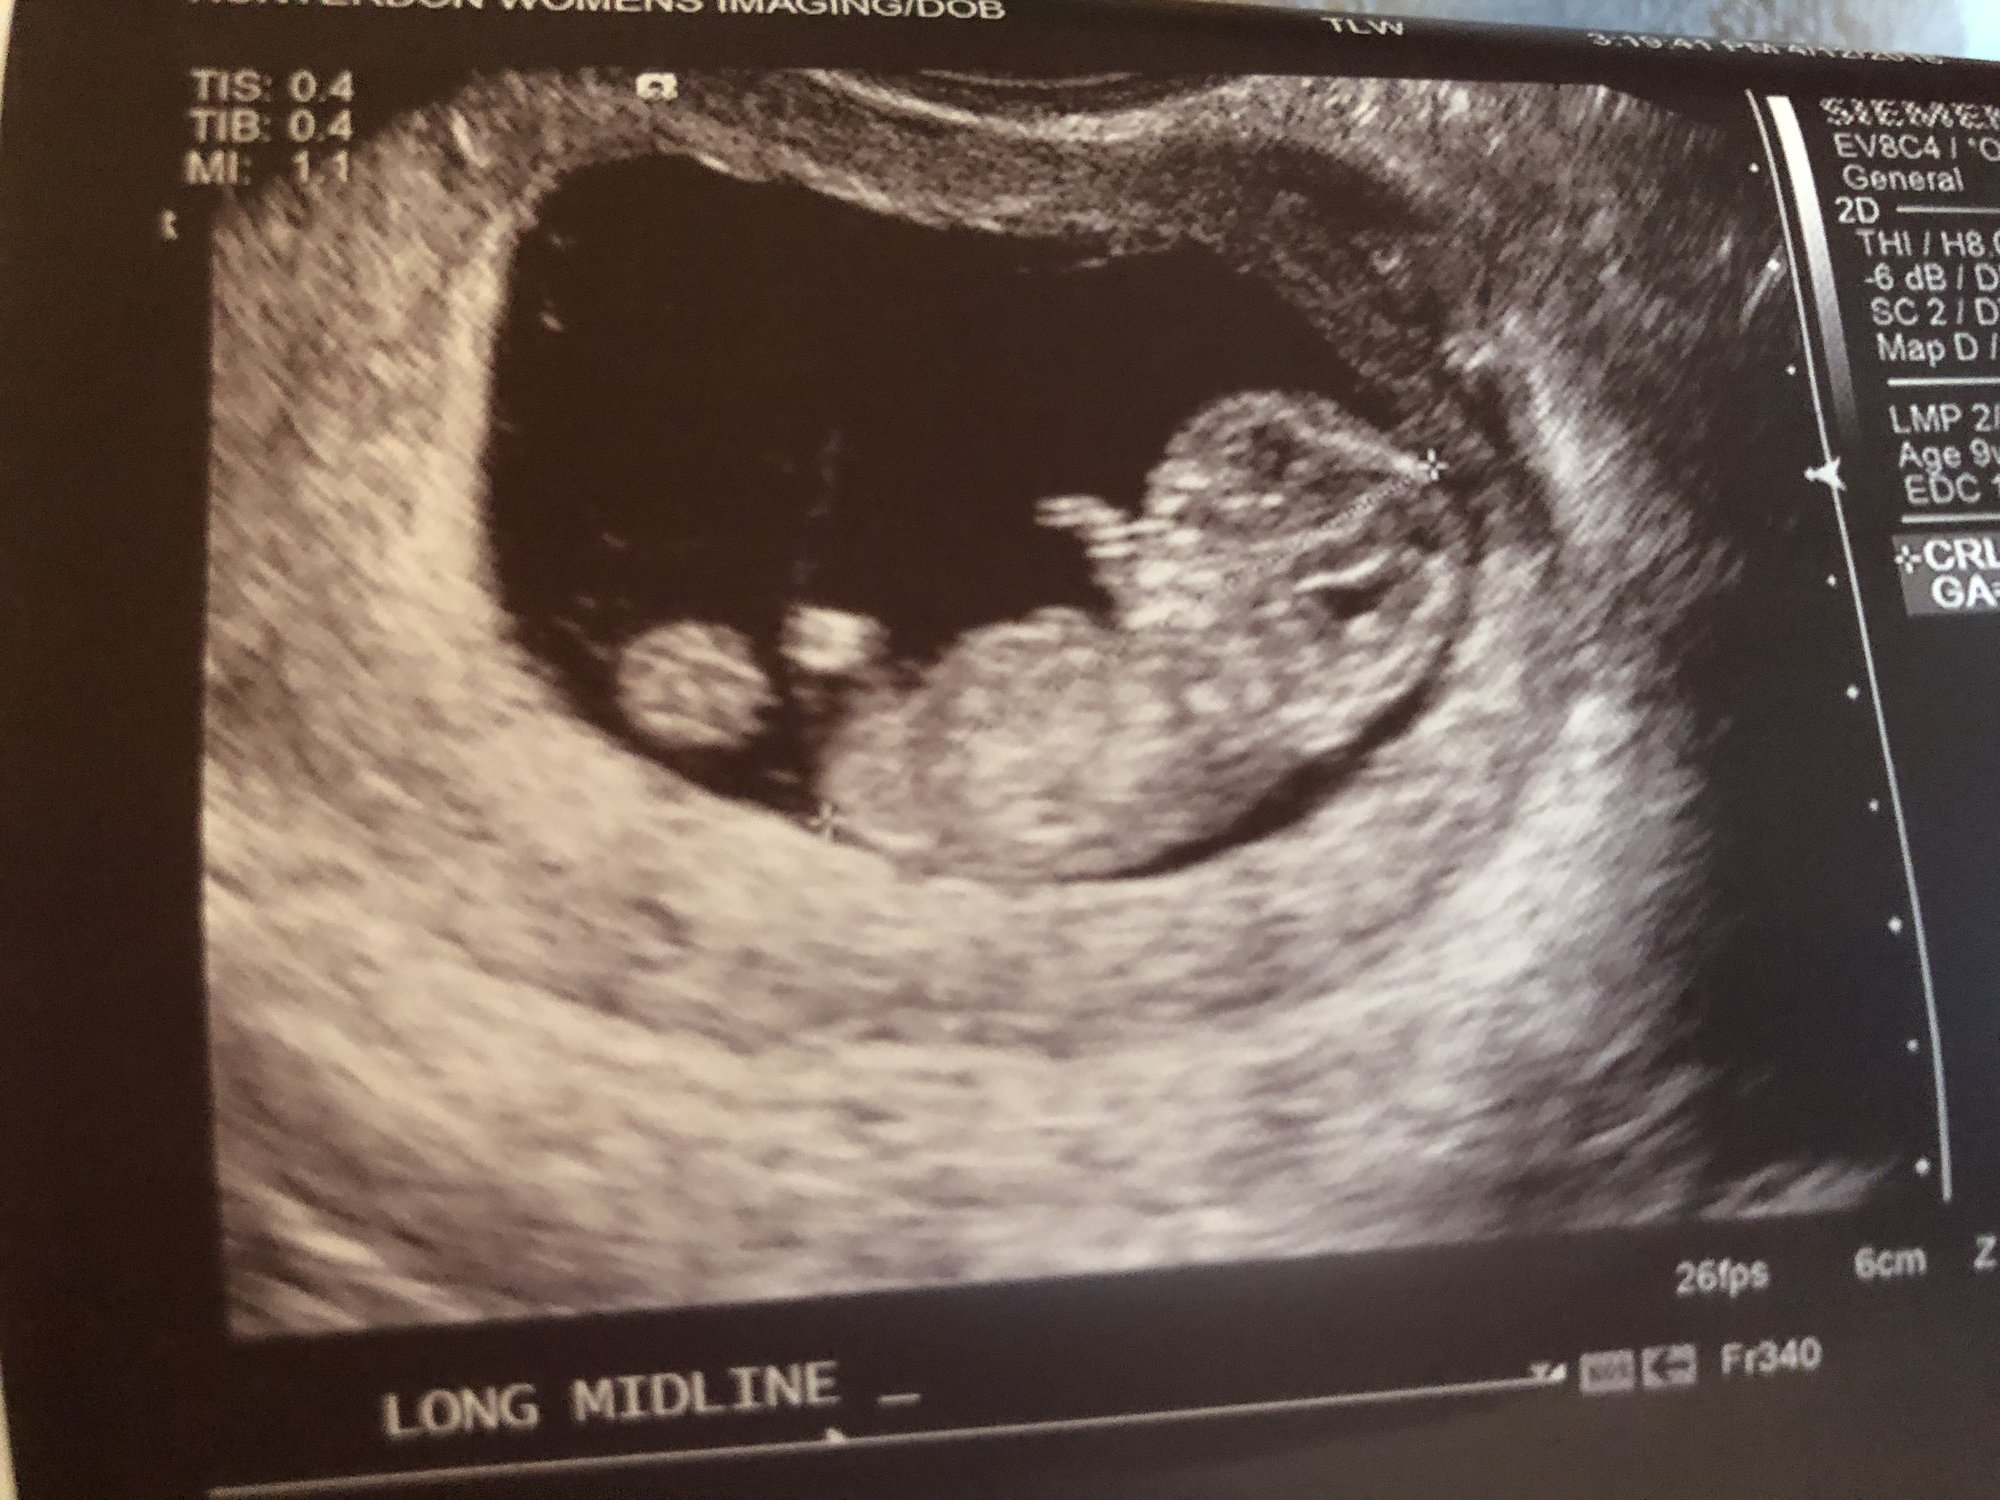

Hi everyone, 6 weeks ultrasound. I’m scheduled back for an 8 weeks ultrasound. Doctor said it’s twins but one is smaller than the other one that we had to wait and see if the other progresses. Has anyone had a similar situation? This is my 3rd pregnancy but first time twins.